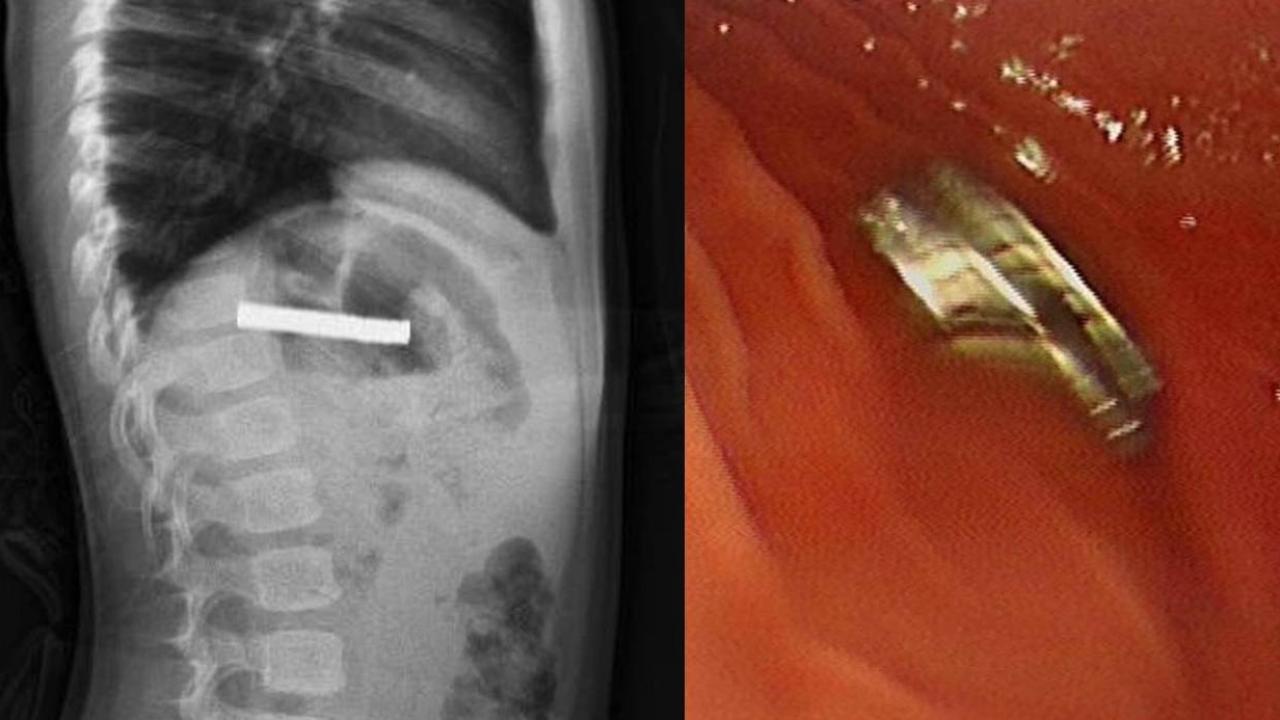

Fırat Üniversitesi Çocuk Gastroenteroloji, Hepatoloji ve Beslenme Bilim Dalı Başkanı Prof. Dr. Yaşar Doğan tarafından yapılan endoskopik işlemle, çocuğun yemek borusuna yapışan 19 mıknatıs tek tek çıkarıldı.

Yemek borusu ve mide girişinde hasar oluştu

Uzun süre yemek borusunda kalan mıknatısların, yemek borusu ve mide girişinde zedelenmelere yol açtığı öğrenildi. Başarılı operasyonun ardından çocuğun sağlık durumunun iyi olduğu ve kısa sürede taburcu edildiği belirtildi.